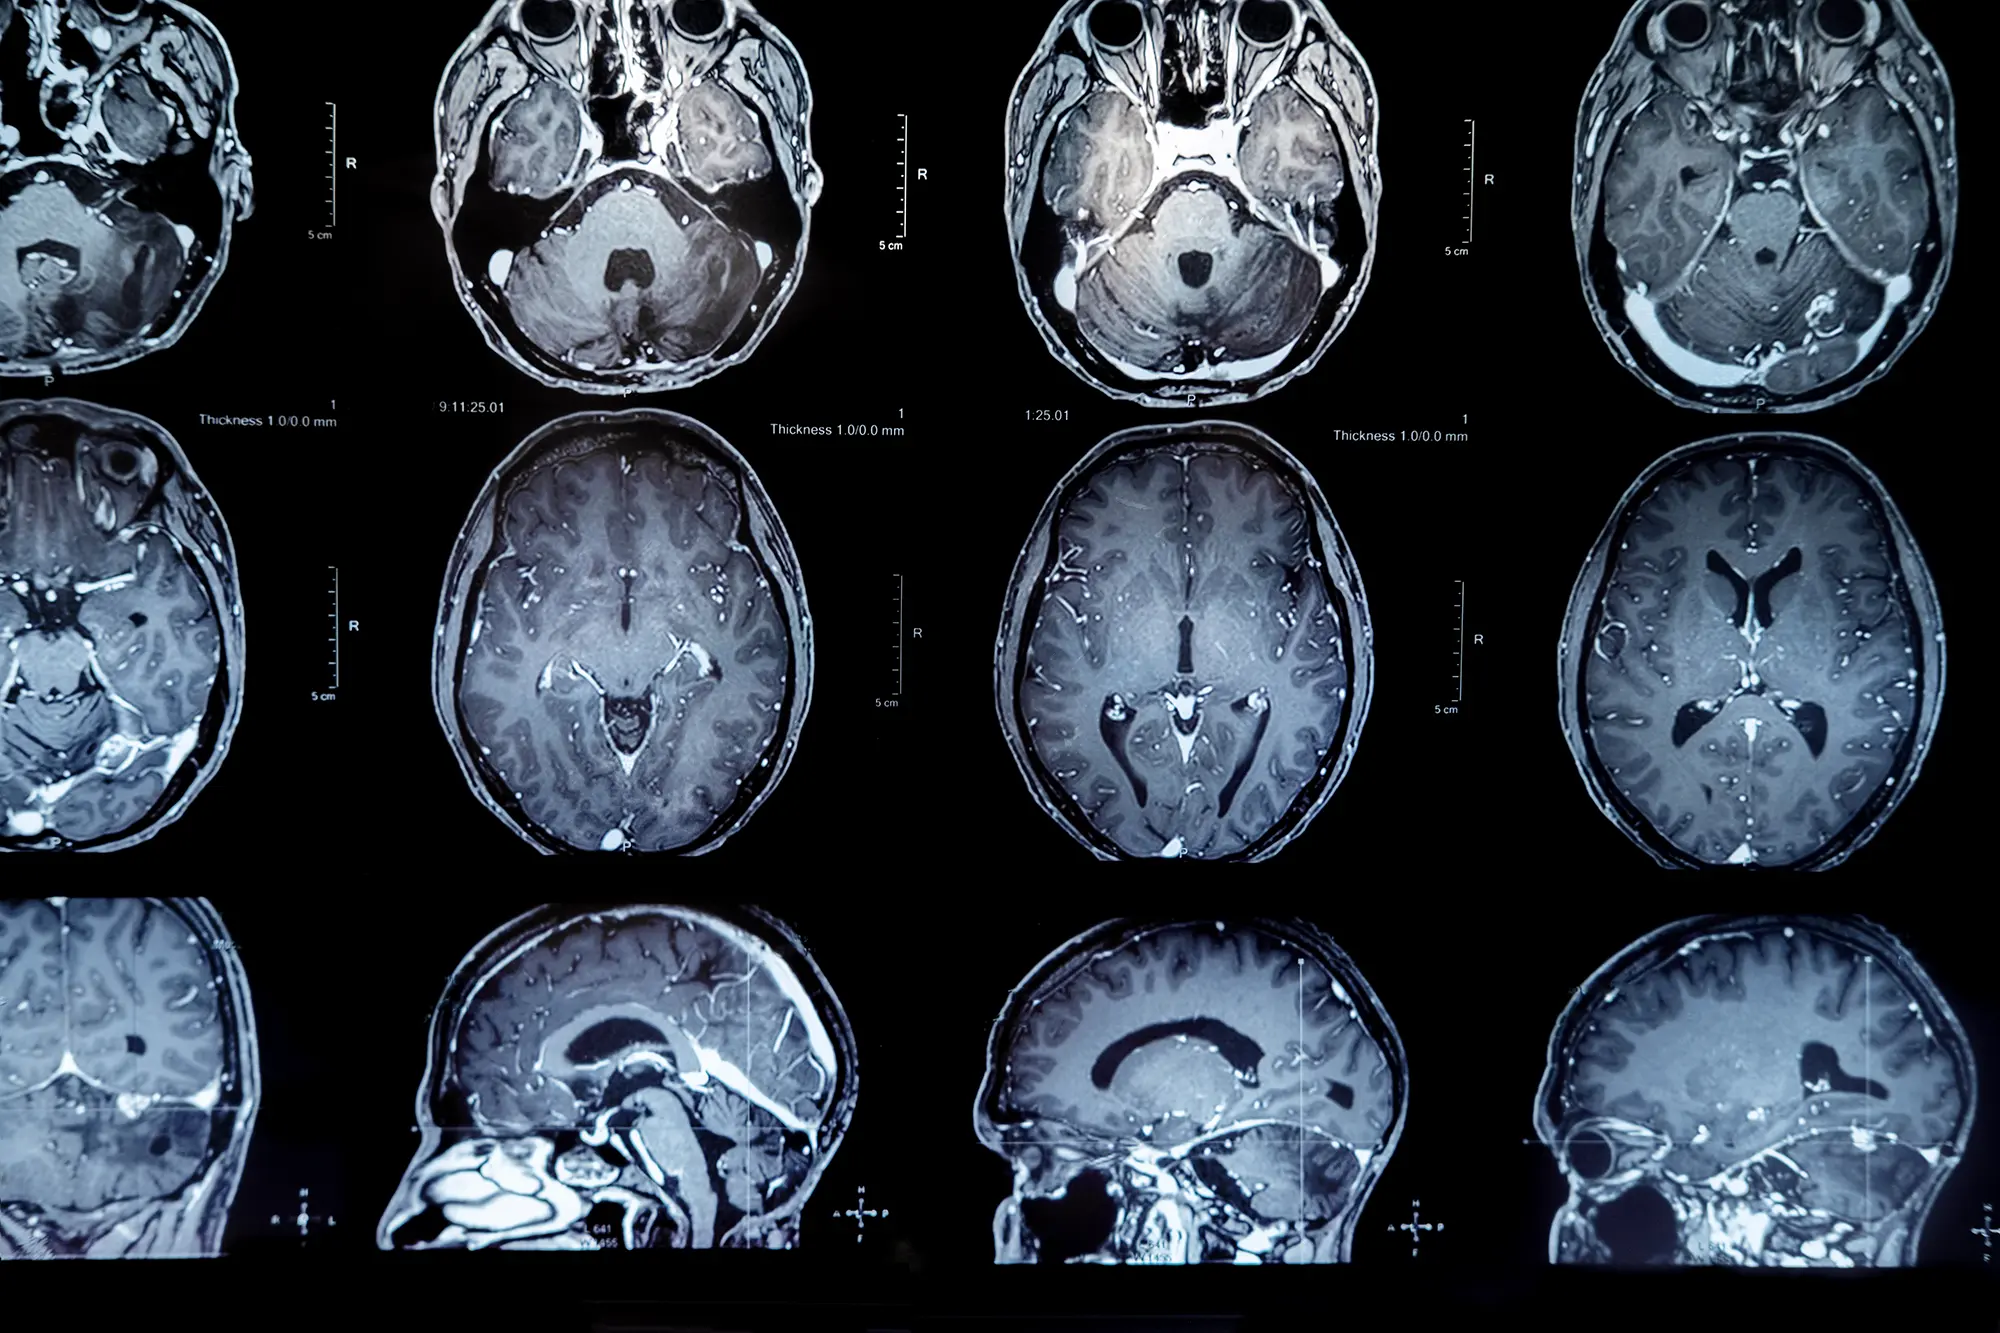

Erken Tanı ve Görüntüleme Önemli

Tanı sürecinde nörolojik muayene sonrası Manyetik Rezonans Görüntüleme (MRG) ve gerektiğinde biyopsi ile tümörün tipi ve derecesinin belirlenebildiğini açıklayan Prof. Dr. Emmez, “Erken tanı tedavi başarısında kritik rol oynar ve kalıcı hasar riskini azaltır” dedi.